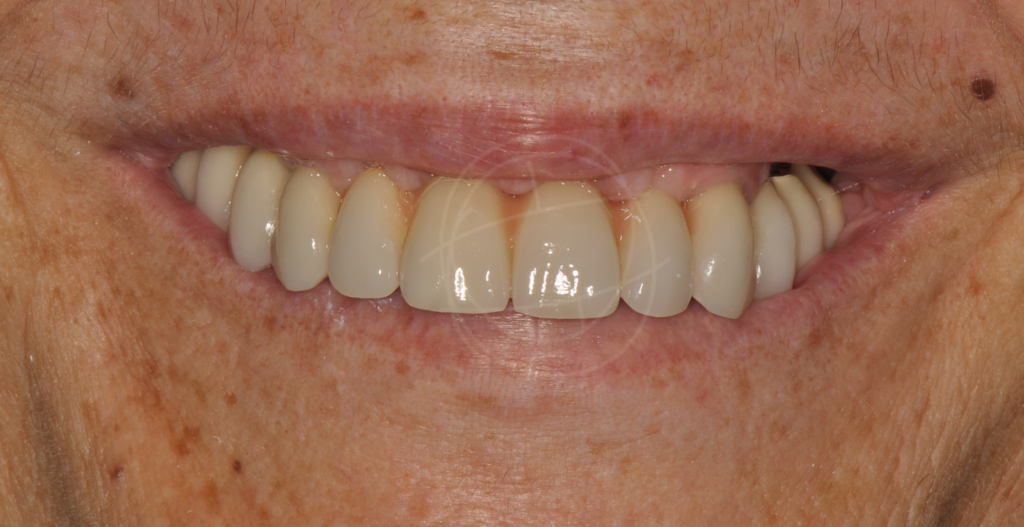

Φυσική εμφάνιση και αίσθηση

Μοιάζουν απόλυτα με φυσικά δόντια σε εμφάνιση και λειτουργία — συνήθως κανείς δεν καταλαβαίνει τη διαφορά.

Αύξηση αυτοπεποίθησης

Ένα σταθερό και όμορφο χαμόγελο βοηθά σημαντικά στην αυτοεκτίμηση και στην καθημερινότητα.